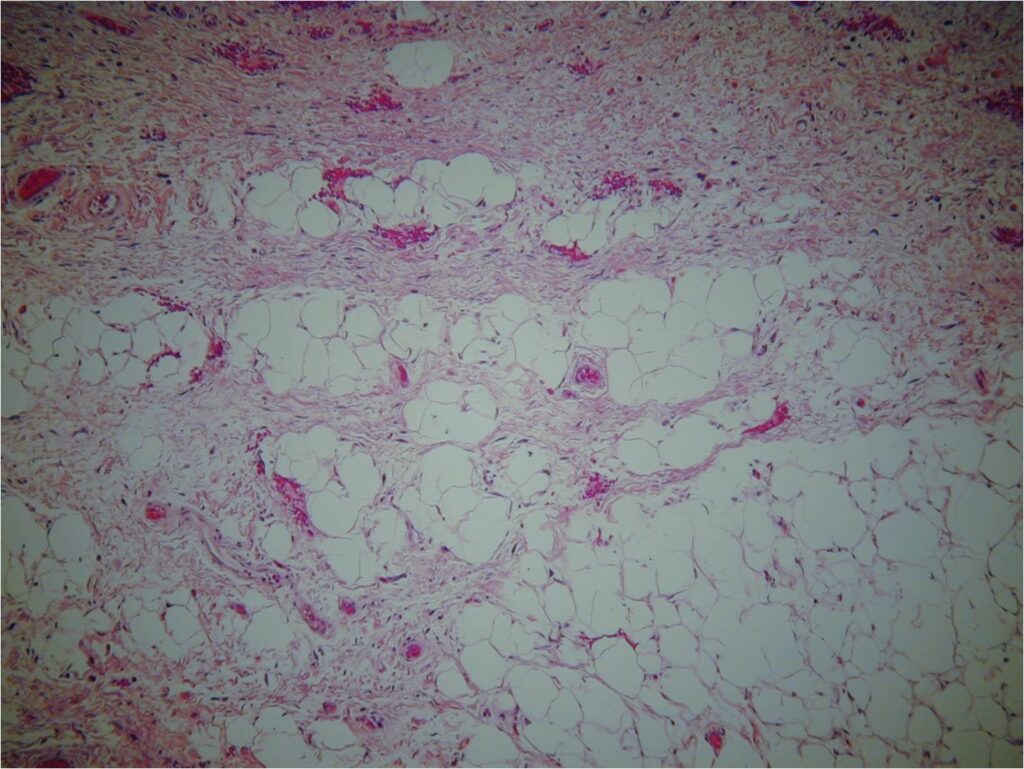

Microscopic Pathology (Fig. 6, 7, 8)

• Atypical stromal cells and lipoblasts in the context of mature fat

• Lipoblasts are immature fat cells often with a bizarre displaced nucleus (the nuclei of benign fat cells are usually very thin and displaced to periphery of cell membrane)

• Often with a prominent fibrous component

• The fat cells are often different sizes and shapes

Fig. 6-8 Microscopic Pathology. Low (Fig. 6), medium (Fig. 7) and high (Fig. 8) magnification H & E slides. Atypical stromal cells and lipoblasts in the context of mature fat. Often with a prominent fibrotic component and stranding. Higher magnification shows disorganized stromal cells and hyperchromasia of nuclei.